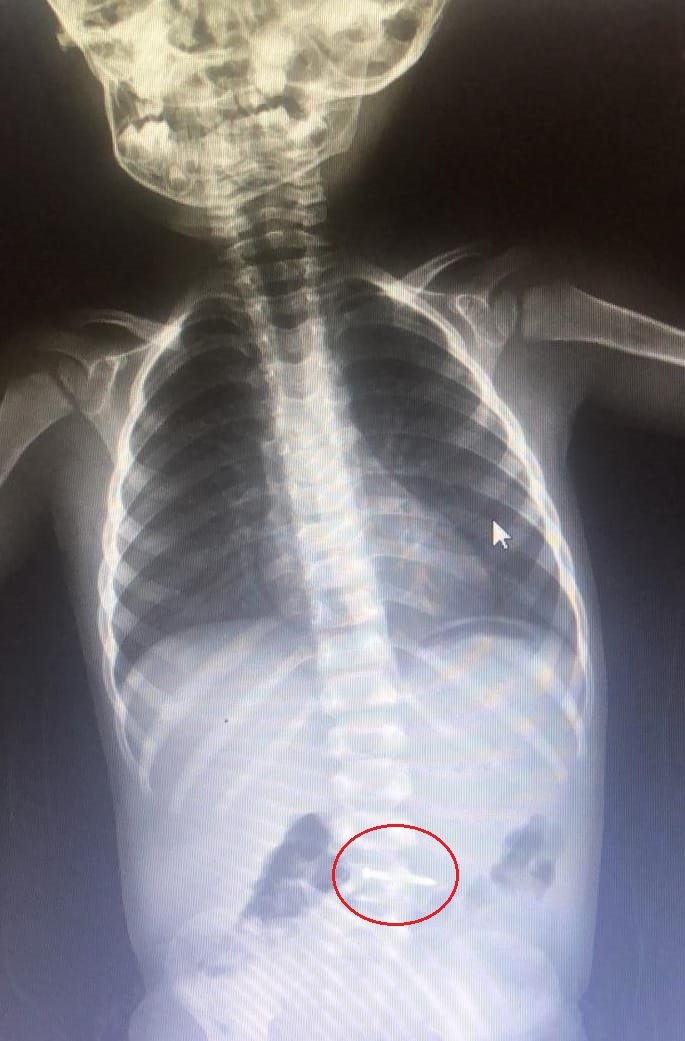

BURSA'nın İnegöl ilçesinde, oyun oynarken yerde bulduğu çiviyi yutan Asil K. (2), kaldırıldığı hastanede tedaviye alındı.

Olay, saat 10.30 sıralarında Mesudiye Mahallesi Sakin Sokak'ta bulunan bir evde meydana geldi. Asil K., babaannesi mutfaktayken, oyun oynadığı odada yerde bulduğu çiviyi ağzına atarak yuttu. Odaya giren babaanne durumu fark edince, dışarıda olan oğlu ve gelinine haber verdi. Araçla İnegöl Devlet Hastanesi'ne kaldırılan bebek, buradaki tetkiklerinin ardından sevk edildiği, Bursa Yüksek İhtisas Eğitim ve Araştırma Hastanesi'nde tedaviye alındı. Bebeğin yuttuğu çiviyi, doğal yollarla çıkarmasının bekleneceği, aksi takdirde ameliyatla midesinden alınacağı öğrenildi.